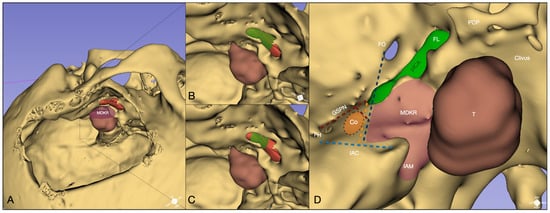

NIR Indocyanine–White Light Overlay Visualization for Neuro-Oto-Vascular Preservation During Anterior Transpetrosal Approaches: A Technical Note

Objectives: Anterior petrosectomy is a challenging neurosurgical procedure requiring precise identification and preservation of multiple critical structures. This technical note explores the feasibility of using real-time near-infrared indocyanine green (NIR-ICG) fluorescence with white light overlay to enhance visualization of the petrous internal carotid artery (ICA) during transpetrosal drilling. We aimed to assess its utility for planning and performing modified Dolenc–Kawase drilling. Methods: We integrated NIR-ICG and white light overlay using a robotic microscope with simultaneous visualization capabilities. This technique was applied to improve neurovascular preservation and skull base landmark identification. Intraoperative video frames and images were captured during an anterior transpetrosal approach for a petroclival meningioma, with technical details, surgical time, and feedback documented. Results: Real-time NIR-ICG with white light overlay successfully identified the posterior genu, horizontal petrosal segment, anterior genu, and superior petrosal sinus. It facilitated precise localization of cochlear landmarks, enabling tailored drilling of the Dolenc–Kawase rhomboid according to patient anatomy and accommodating potential anatomical variants. Conclusions: This approach could enhance intraoperative safety and improve exposure, possibly reducing neurovascular risks without extending operative time. It may serve as a valuable adjunct for complex skull base surgeries. Full article

Figure 1